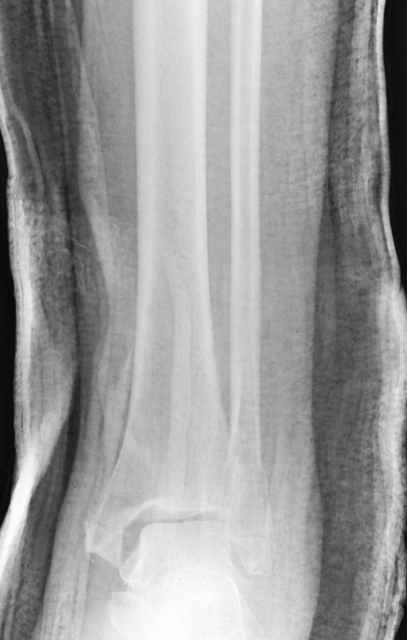

Pilon fracture:

ET> ЕЧ При подобных переломах фиксация малоберцовой кости обеспечивает

ET> низведение латерального тибиального фрагмента - появляется ориентир для

-Появляется ориентир и остов, на чем можно строить восстановление, почему сперва малоберцовую, впервые обьяснили и описали (Pylon type and Ankle fractures) в середине 50х Rienau и Gay.

Восстановливая длину и ротацию малоберцовой кости, затем относительно легче произвести реставрацию остальных элементов перелома дистального эпиметафиза болшеберцовой кости.

первую очередь, затем остальных элементов - стал классическим при лечении данной патолгии. Латеральная колонна (столб), дистальный

конец малоберцевой кости, к нему прикрепляется латеральный суставной фрагмент дистального эпиметафиза большеберцовой кости (как на снимке)

и таранная кость, которые при репозиции малоберцовой кости репонируются автоматически.

Из работ Ramsey and Hamilton, Yablon et., укорочения на 1мм

малоберцовой кости, уменьшает на 42% контактную поверхность между

малоберцевой и таранной кости, которое в свою очередь приводит к

увеличению давления на остальные части суставной поверхности, что

является предпосылкой раннего артроза.